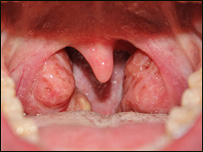

تانسلونه (هډي)، چې عام وګړي يې په ستوني کې اضافي غوښې بولي، په بدن کې دمکروب پروړاندې دفاعي دنده پرمخ بيايي، چې له دې امله ډېری وخت پخپله مکروبي کيږي. روغتيايي کارپوهان دتانسلونومکروبي کېدل نه يواځې ساري بلکې يوه ارثي ناروغي هم ګڼي. دستوني، غوږ او پزي متخصص ډاکتر صديق الله رښتين دنورو ترڅنګ د خولې او غاښونو پاکوالي ته نه پاملرنه هم ددې ناروغۍ لامل وګاڼه. هغه کسان، چې تانسلونه يې مکروبي شوي وي، دسختې تبې او ځان دردۍ ترڅنګ يې د ستوني لاندنۍ برخه کې پړسوب هم ليدل کيږي.  | | | دتانسلونومکروبي کېدل نه يواځې ساري بلکې يوه ارثي ناروغي هم ګڼي. |

که ددې ناروغۍ په درملنه کې بې پروايي وشي،مکروب يې په وينه کې ګډ او دروماتيزم او نورو ناروغيو دپيداکېدولامل هم کيږي. ددې ناروغۍ څخه دمخنيوي په موخه روغتيايي کارپوهان دخولې دپاک ساتلوترڅنګ له ډېروغوړو، خوږواو مرچوخوړلوډډه کول ګټوربولي. |